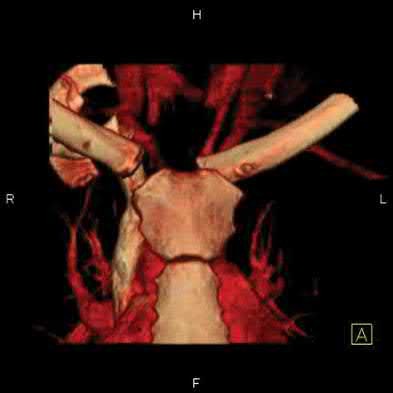

1024) An 18-year-old football player crossing the field to make a catch is hit on the shoulder and upper chest by the tackler and falls to the

ground with immediate pain throughout the shoulder region. The emergency department physician obtains the radiographs, CT scan, and 3-dimensional reconstructions seen in Figures 118a through 118e. What is the next step in management?

1. Obtain an MRI scan of the shoulder.

2. Place the arm in a sling for comfort and treat the injury nonsurgically.

3. Perform closed reduction in the emergency department.

4. Perform closed reduction in the operating room.

5. Perform open reduction using Kirschner wires to hold the joint reduced.

Corrent answer: 4

The player has sustained a posterior sternoclavicular dislocation. The CT scans show the medial end of the clavicle in close proximity to the aorta. An MRI scan will add no diagnostic information and might delay treatment. Nonsurgical management of an anterior sternoclavicular dislocation is often appropriate, but given the proximity of the clavicle to the aorta and airway, reduction of the dislocation is recommended to prevent vascular injury. While reduction is indicated, performing the reduction in the emergency department is not recommended because of the vascular injury or the need to perform an open reduction. Performing the procedure in the operating room with a thoracic surgeon available is recommended. Usually a closed reduction is stable, but if open reduction is necessary, Kirschner wires should be avoided to avoid the chance of migration of the implants.